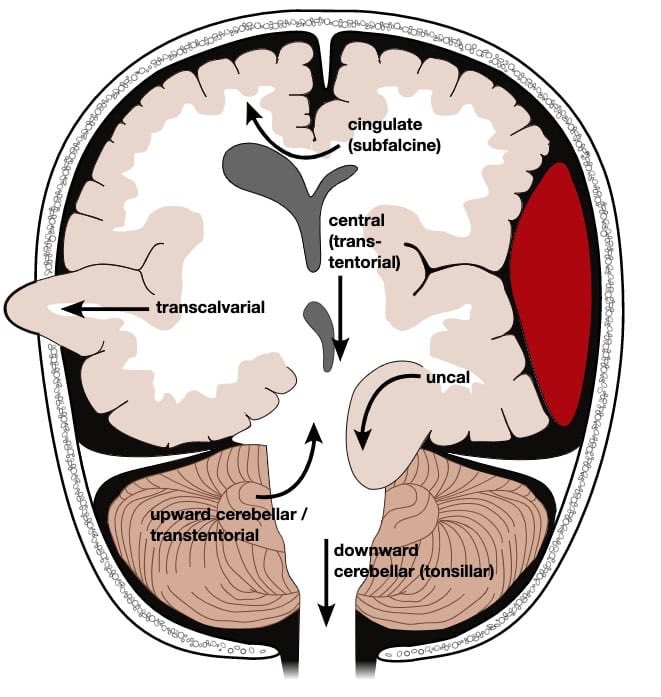

🛑لازم نتأكد من عدم وجود الآتي:

✳️ Midline shift➕herniation

✳️فقدان Grey-white matter differentiation ⬅️ لأن فقدانها يدل على واحدة من العلامات المبكرة للجلطة